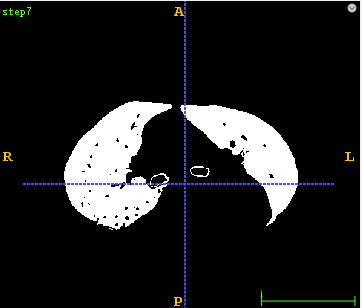

3、肺组织分割代码详解 3.1、 首先采用固定阈值区分肺组织和身体其它组织,设置固定阈值为-300。

3.2、 然后采用水漫金山法将肺组织和人体其它组织填充成一个区域。

3.3、 然后对固定阈值结果和水漫金山法结果先进行逻辑异或操作,然后再对其结果进行取反。

3.4、 对肺部内部区域进行填小洞操作。

3.5、采用连通域分析,去除小于最大物体一定比例的小目标物体。

3.6、采用区域生长得到气管分割结果。

3.7、 将第3.5步结果减去第3.6步结果。

3.8、 首先采用形态学开操作去除多余的边界区域,然后再采用形态学闭操作平滑肺组织轮廓,并填充肺部中中型空洞区域。

3.9、将得到的Mask图像与原始图像进行逻辑与操作得到最后的肺部分割结果图像。

def lungSegment(pathDicom): sitk_src = dicomseriesReader(pathDicom) # 1 sitk_seg = BinaryThreshold(sitk_src, lowervalue=-300, uppervalue=2000) sitk.WriteImage(sitk_seg, 'step1.mha') # 2 sitk_floodfilled = FloodFilled(sitk_seg) sitk.WriteImage(sitk_floodfilled, 'step2.mha') # 3 sitk_xorop = sitk.XorImageFilter() sitk_mask1 = sitk_xorop.Execute(sitk_seg, sitk_floodfilled) sitk_notop = sitk.NotImageFilter() sitk_mask2 = sitk_notop.Execute(sitk_mask1) sitk.WriteImage(sitk_mask2, 'step3.mha') # 4 sitk_mask3 = FillHole(sitk_mask2) sitk.WriteImage(sitk_mask3, 'step4.mha') # 5 sitk_mask4 = RemoveSmallConnectedCompont(sitk_mask3, 0.2) sitk.WriteImage(sitk_mask4, 'step5.mha') # 6 segtrachea lstSeeds = [] seed1 = [246, 268, 835] seed2 = [241, 287, 798] seed3 = [272, 277, 798] lstSeeds.append(seed1) lstSeeds.append(seed2) lstSeeds.append(seed3) sitk_tracheamask = RegionGrowThreshold(sitk_src, lstSeeds, -1024, -900) sitk.WriteImage(sitk_tracheamask, 'step6.mha') # 7 lung reduce trachea array_tracheamask = sitk.GetArrayFromImage(sitk_tracheamask) array_mask4 = sitk.GetArrayFromImage(sitk_mask4) array_mask4 = array_mask4 - array_tracheamask sitk_mask4 = sitk.GetImageFromArray(array_mask4) sitk_mask4.SetDirection(sitk_tracheamask.GetDirection()) sitk_mask4.SetSpacing(sitk_tracheamask.GetSpacing()) sitk_mask4.SetOrigin(sitk_tracheamask.GetOrigin()) sitk.WriteImage(sitk_mask4, 'step7.mha') # 8 sitk_mask4 = MorphologicalOperation(sitk_mask4, kernelsize=3, name='open') sitk_mask5 = MorphologicalOperation(sitk_mask4, kernelsize=9, name='close') sitk.WriteImage(sitk_mask5, 'step8.mha') # 9 sitk_lung = GetMaskImage(sitk_src, sitk_mask5, replacevalue=-1500) sitk.WriteImage(sitk_lung, 'step9.mha') return sitk_lung